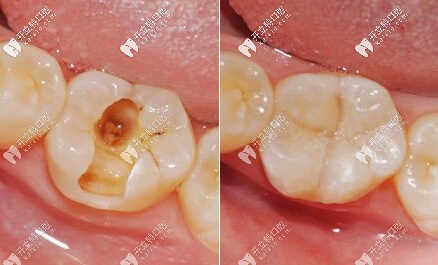

補牙的前后對比圖